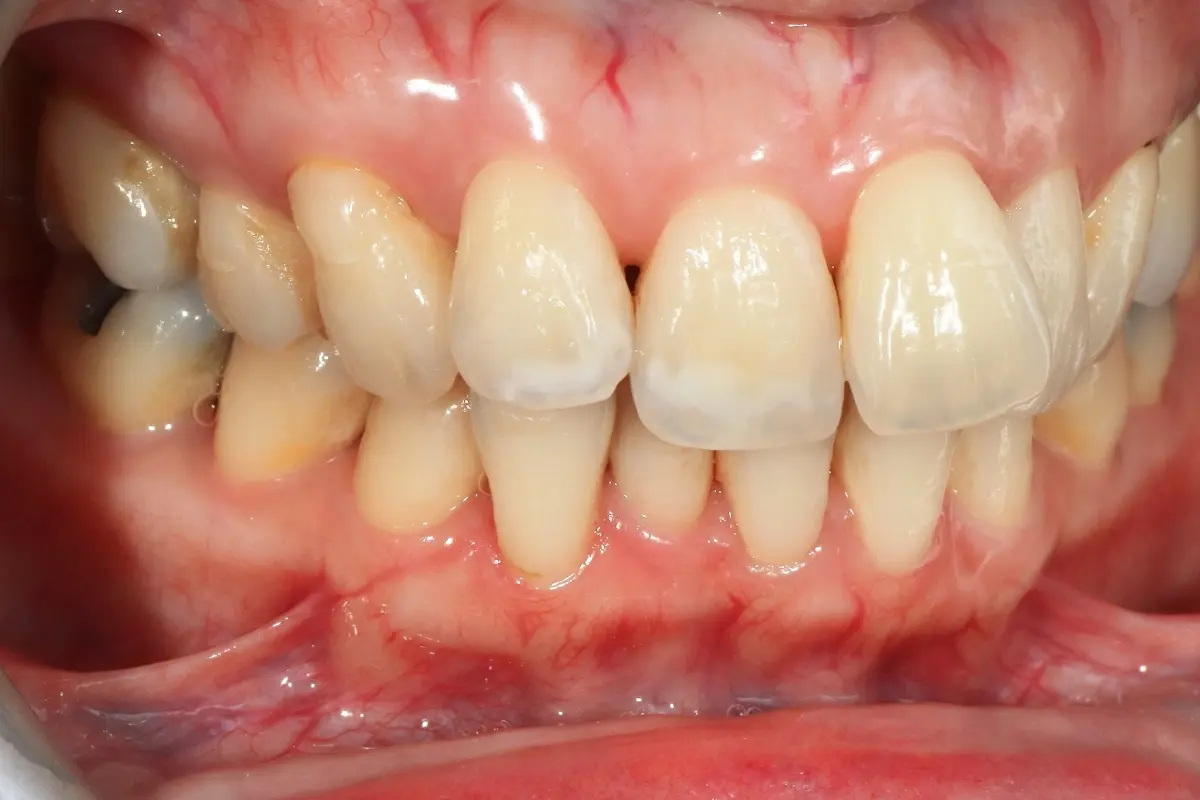

Dentist 陳昕 全口照護醫師 看診項目 前牙美學仿生樹脂補牙/全科牙醫 學經歷 臺北醫學大學牙醫系學士 前天主教新店耕莘醫院醫師 前臺北榮民總醫院醫師 亞洲齒列再生研究學會Advance植牙補綴專科訓練 微光私塾牙周雷射微創治療技術訓練 臺灣牙醫顯微美學治療學會會員醫師 中華審美牙醫學會會員醫師 CASE 案例分享 滲透型樹脂修復 主治醫師 陳昕 治療時間 單次療程 主訴 想處理前牙白白的色斑 前牙美學/仿生美學樹脂 主治醫師 陳昕 治療時間 單次療程 主訴 牙齒整齊,但門牙中間縫隙明顯,影響笑容美觀 前牙美學/陶瓷貼片 主治醫師 陳昕 治療時間 約1個月 主訴 兩顆門牙缺角,想要重建外觀 前牙美學/滲透型樹脂修復 主治醫師 陳昕 治療時間 單次療程 主訴 門牙有長期存在的白斑與表面不平整,影響外觀與自信 前牙美學/仿生美學樹脂 主治醫師 陳昕 治療時間 約兩週 主訴 矯正後的黑三角縫問題 前牙美學/仿生美學樹脂 主治醫師 陳昕 治療時間 約三週 主訴 因牙周病產生的黑三角縫 前牙美學/牙冠增長術、仿生全瓷牙冠 主治醫師 陳昕 治療時間 約6個月 主訴 牙齒排列不整、假牙外觀不自然 前牙美學/仿生美學樹脂 主治醫師 陳昕 治療時間 約兩週 主訴 露齒笑時黑三角縫明顯,覺得不好看 前牙美學/仿生美學樹脂+噴砂美白 主治醫師 陳昕 治療時間 約兩週 主訴 露齒笑時有不好看的黑三角縫,容易有茶垢沉澱,讓縫隙更明顯 牙齒美白/噴砂美白+冷光美白 主治醫師 陳昕 治療時間 單次療程 主訴 前牙泛黃且染色明顯,影響外觀與自信 牙齒美白/噴砂美白 主治醫師 陳昕 治療時間 單次療程 主訴 牙齒表面有喝咖啡、抽菸造成的外部染色,影響外觀與自信 點此載入更多 Column 精選文章 FEATURED 精選案例 【牙科修復案例】陶瓷貼片可以做一顆嗎?單顆門牙缺角修復,陶瓷貼片重建自然笑容 2026-01-16 從「假笑」到「自然笑容」的轉變——認識「牙冠增長術」與「仿生全瓷冠」 2025-10-14 Video 精選影音